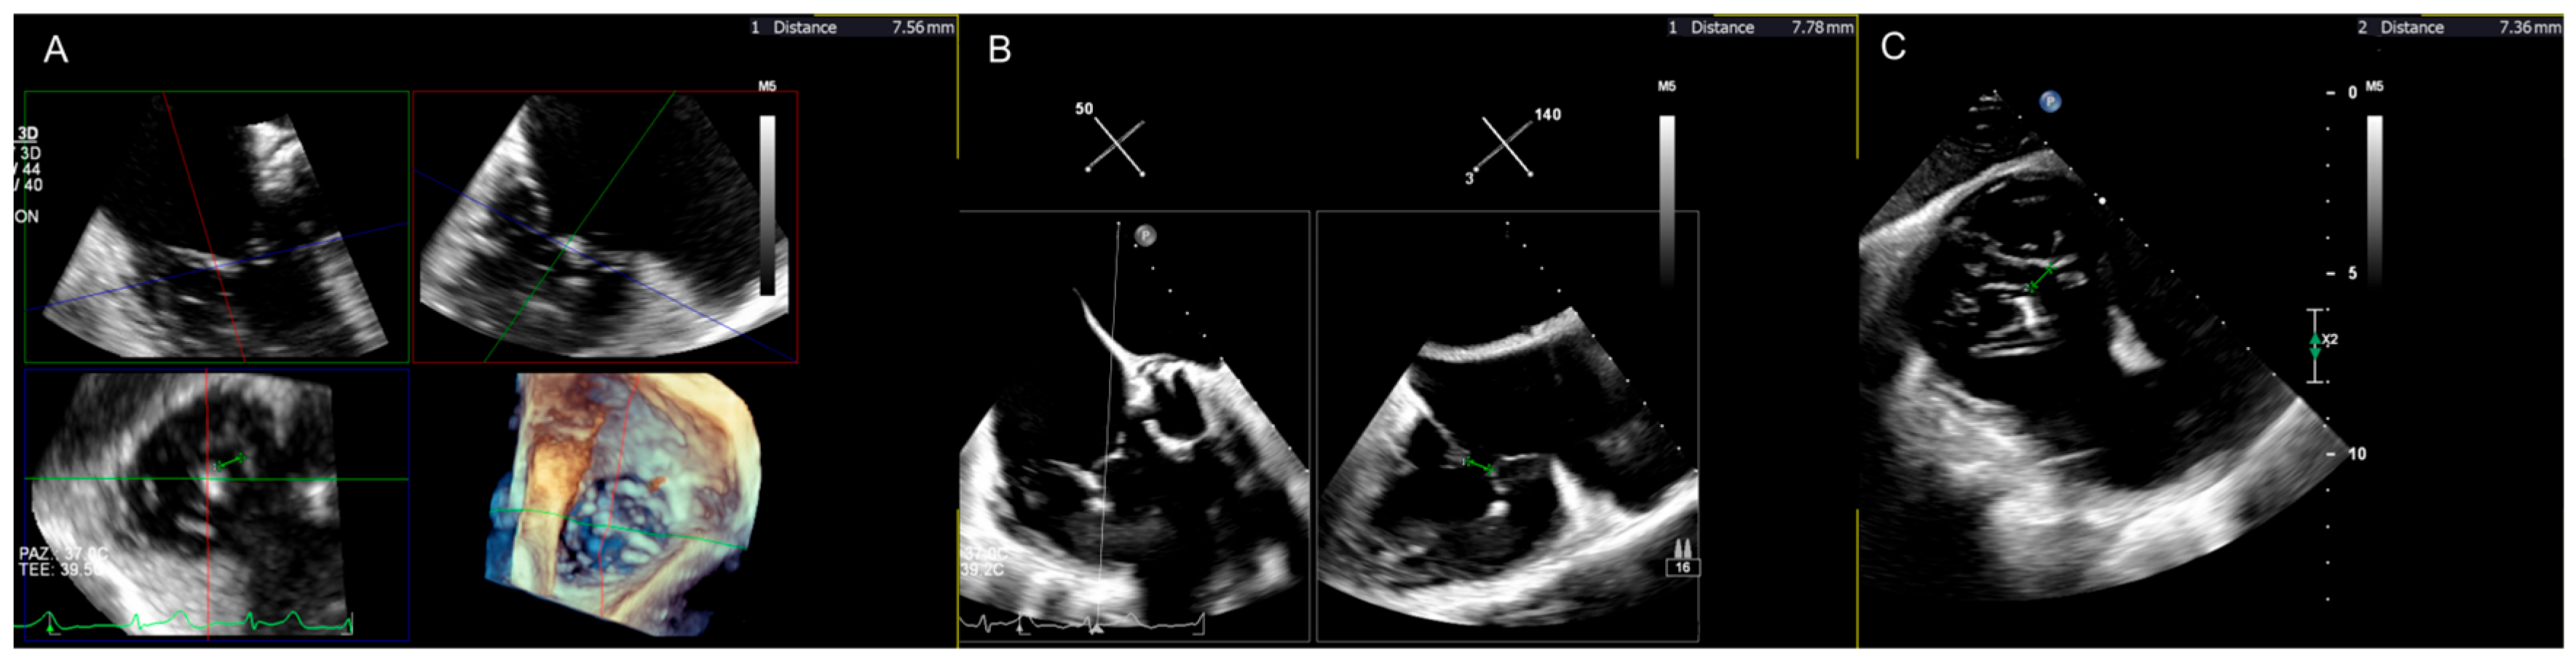

3.1. Transcatheter Edge-to-Edge Repair